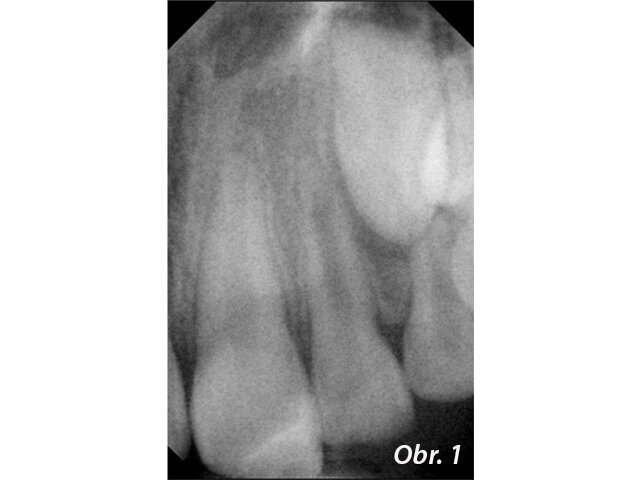

Zánětlivé změny v periapikálních tkáních a současně schopnost hypochloridu rozpouštět měkké tkáně mohou vést ke vzniku prázdného prostoru periapikálně. Pravděpodobnost přetlačení MTA do periapikálního prostoru je pak velká. Vzhledem k biokompatibilitě tohoto materiálu se nejedná o komplikaci, která by ohrožovala výsledek ošetření (obr. 1–4), není však žádoucí. Pokud periapikální tkáně nevytvářejí přirozenou bariéru, která přetlačení MTA brání, je možné takovouto bariéru vytvořit z kolagenu.